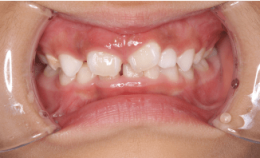

写真②:使用する装置例

写真③:使用する装置例